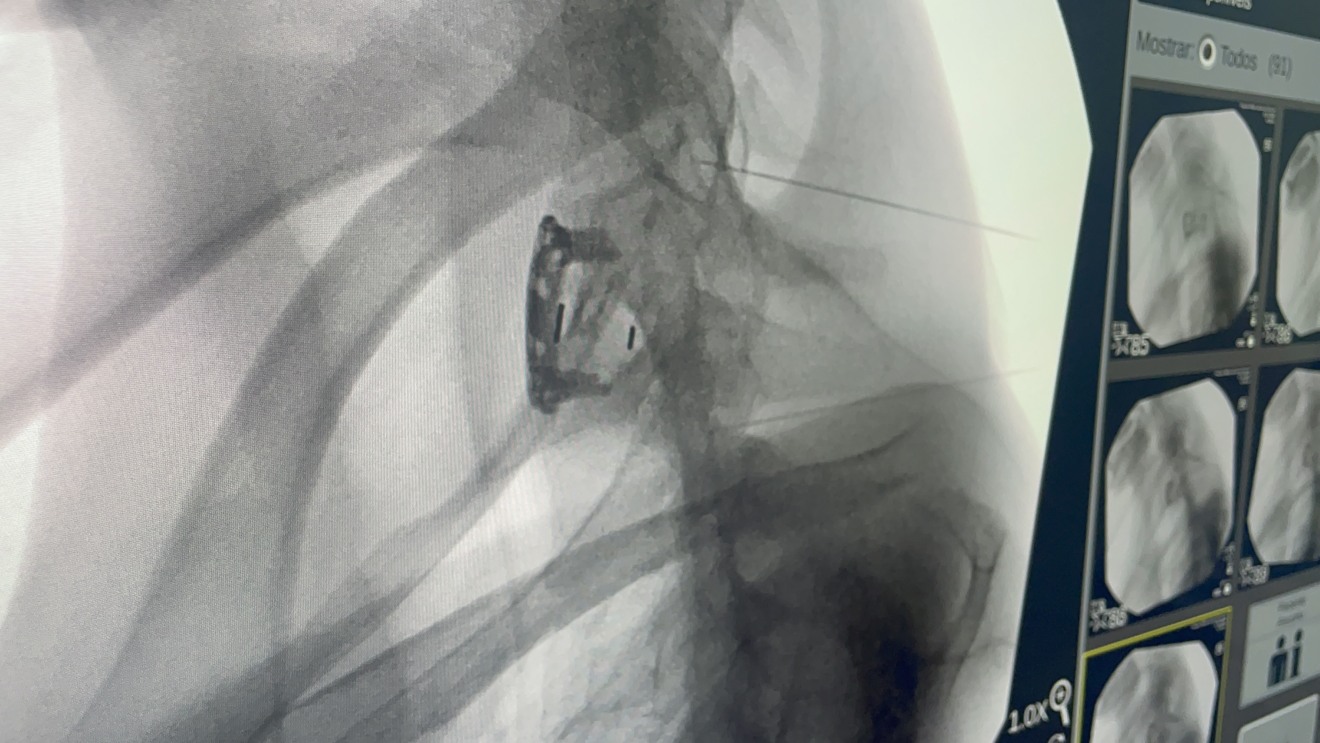

Um tratamento experimental considerado inovador no campo da neurologia foi realizado pela primeira vez em Mato Grosso do Sul na manhã de quarta-feira (21), no Hospital Militar de Área de Campo Grande (HMilACG). A cirurgia utilizou a polilaminina, uma proteína em fase de testes aplicada em pacientes com lesão na medula espinhal.

A cirurgia foi conduzida pelos médicos Wolnei Zeviani, Bruno Cortez e Olavo Franco, com participação de pesquisadores da Universidade Federal do Rio de Janeiro (UFRJ), grupo que desenvolve a polilaminina, sob coordenação da professora Tatiana Sampaio. O procedimento contou ainda com apoio institucional da direção do hospital, comandada pelo tenente-coronel André Antunes Mascarenhas.

Segundo Franco, a polilaminina é um polímero proteico aplicado em dose única diretamente na medula espinhal. “Ela é uma proteína muito grande, que não consegue circular pelo corpo. Por isso, precisa ser aplicada dentro da medula”, explicou.